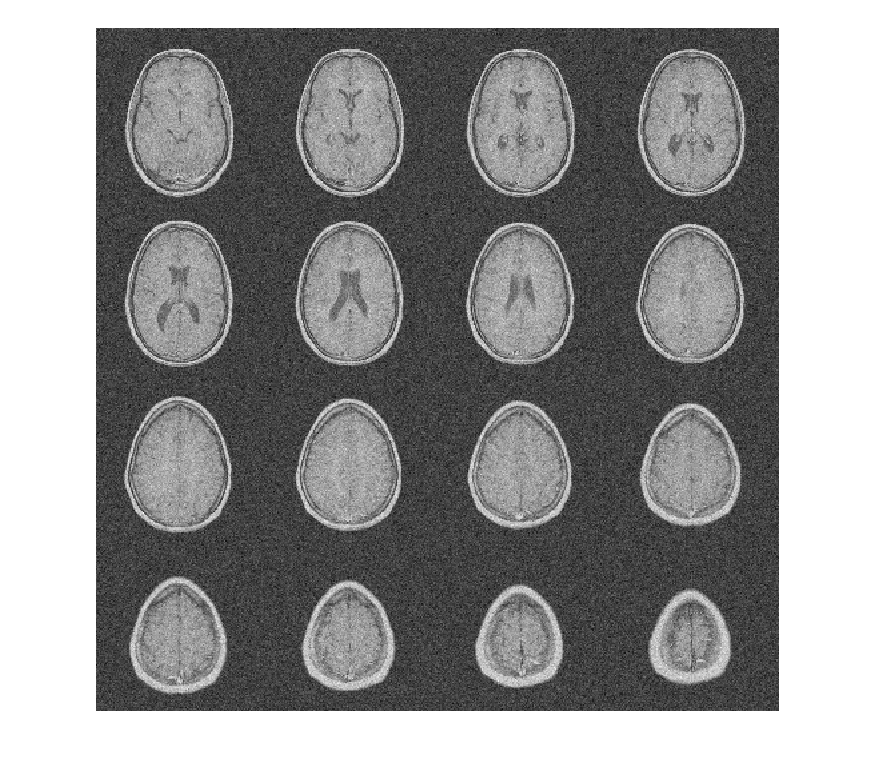

Чтобы продемонстрировать это, рассмотрите набор данных MRI, состоящий из 16 срезов. Гауссов шум со стандартным отклонением 10 был добавлен к исходному набору данных. Отобразите шумный набор данных.

load MRI3D montage(reshape(noisyMRI,[128 128 1 16]),'DisplayRange',[])

Denoise набор данных MRI вниз к уровню 4 с помощью и DTCWT и DWT. Подобные длины фильтра вейвлета используются в обоих случаях. Постройте получившийся ОСШ в зависимости от порога. Отобразите denoised результаты и для DTCWT и для DWT, полученного в лучшем ОСШ.

[imrecDTCWT,imrecDWT] = helperCompare3DDenoising(origMRI,noisyMRI);

figure montage(reshape(imrecDWT,[128 128 1 16]),'DisplayRange',[]) title('DWT Denoised Volume')